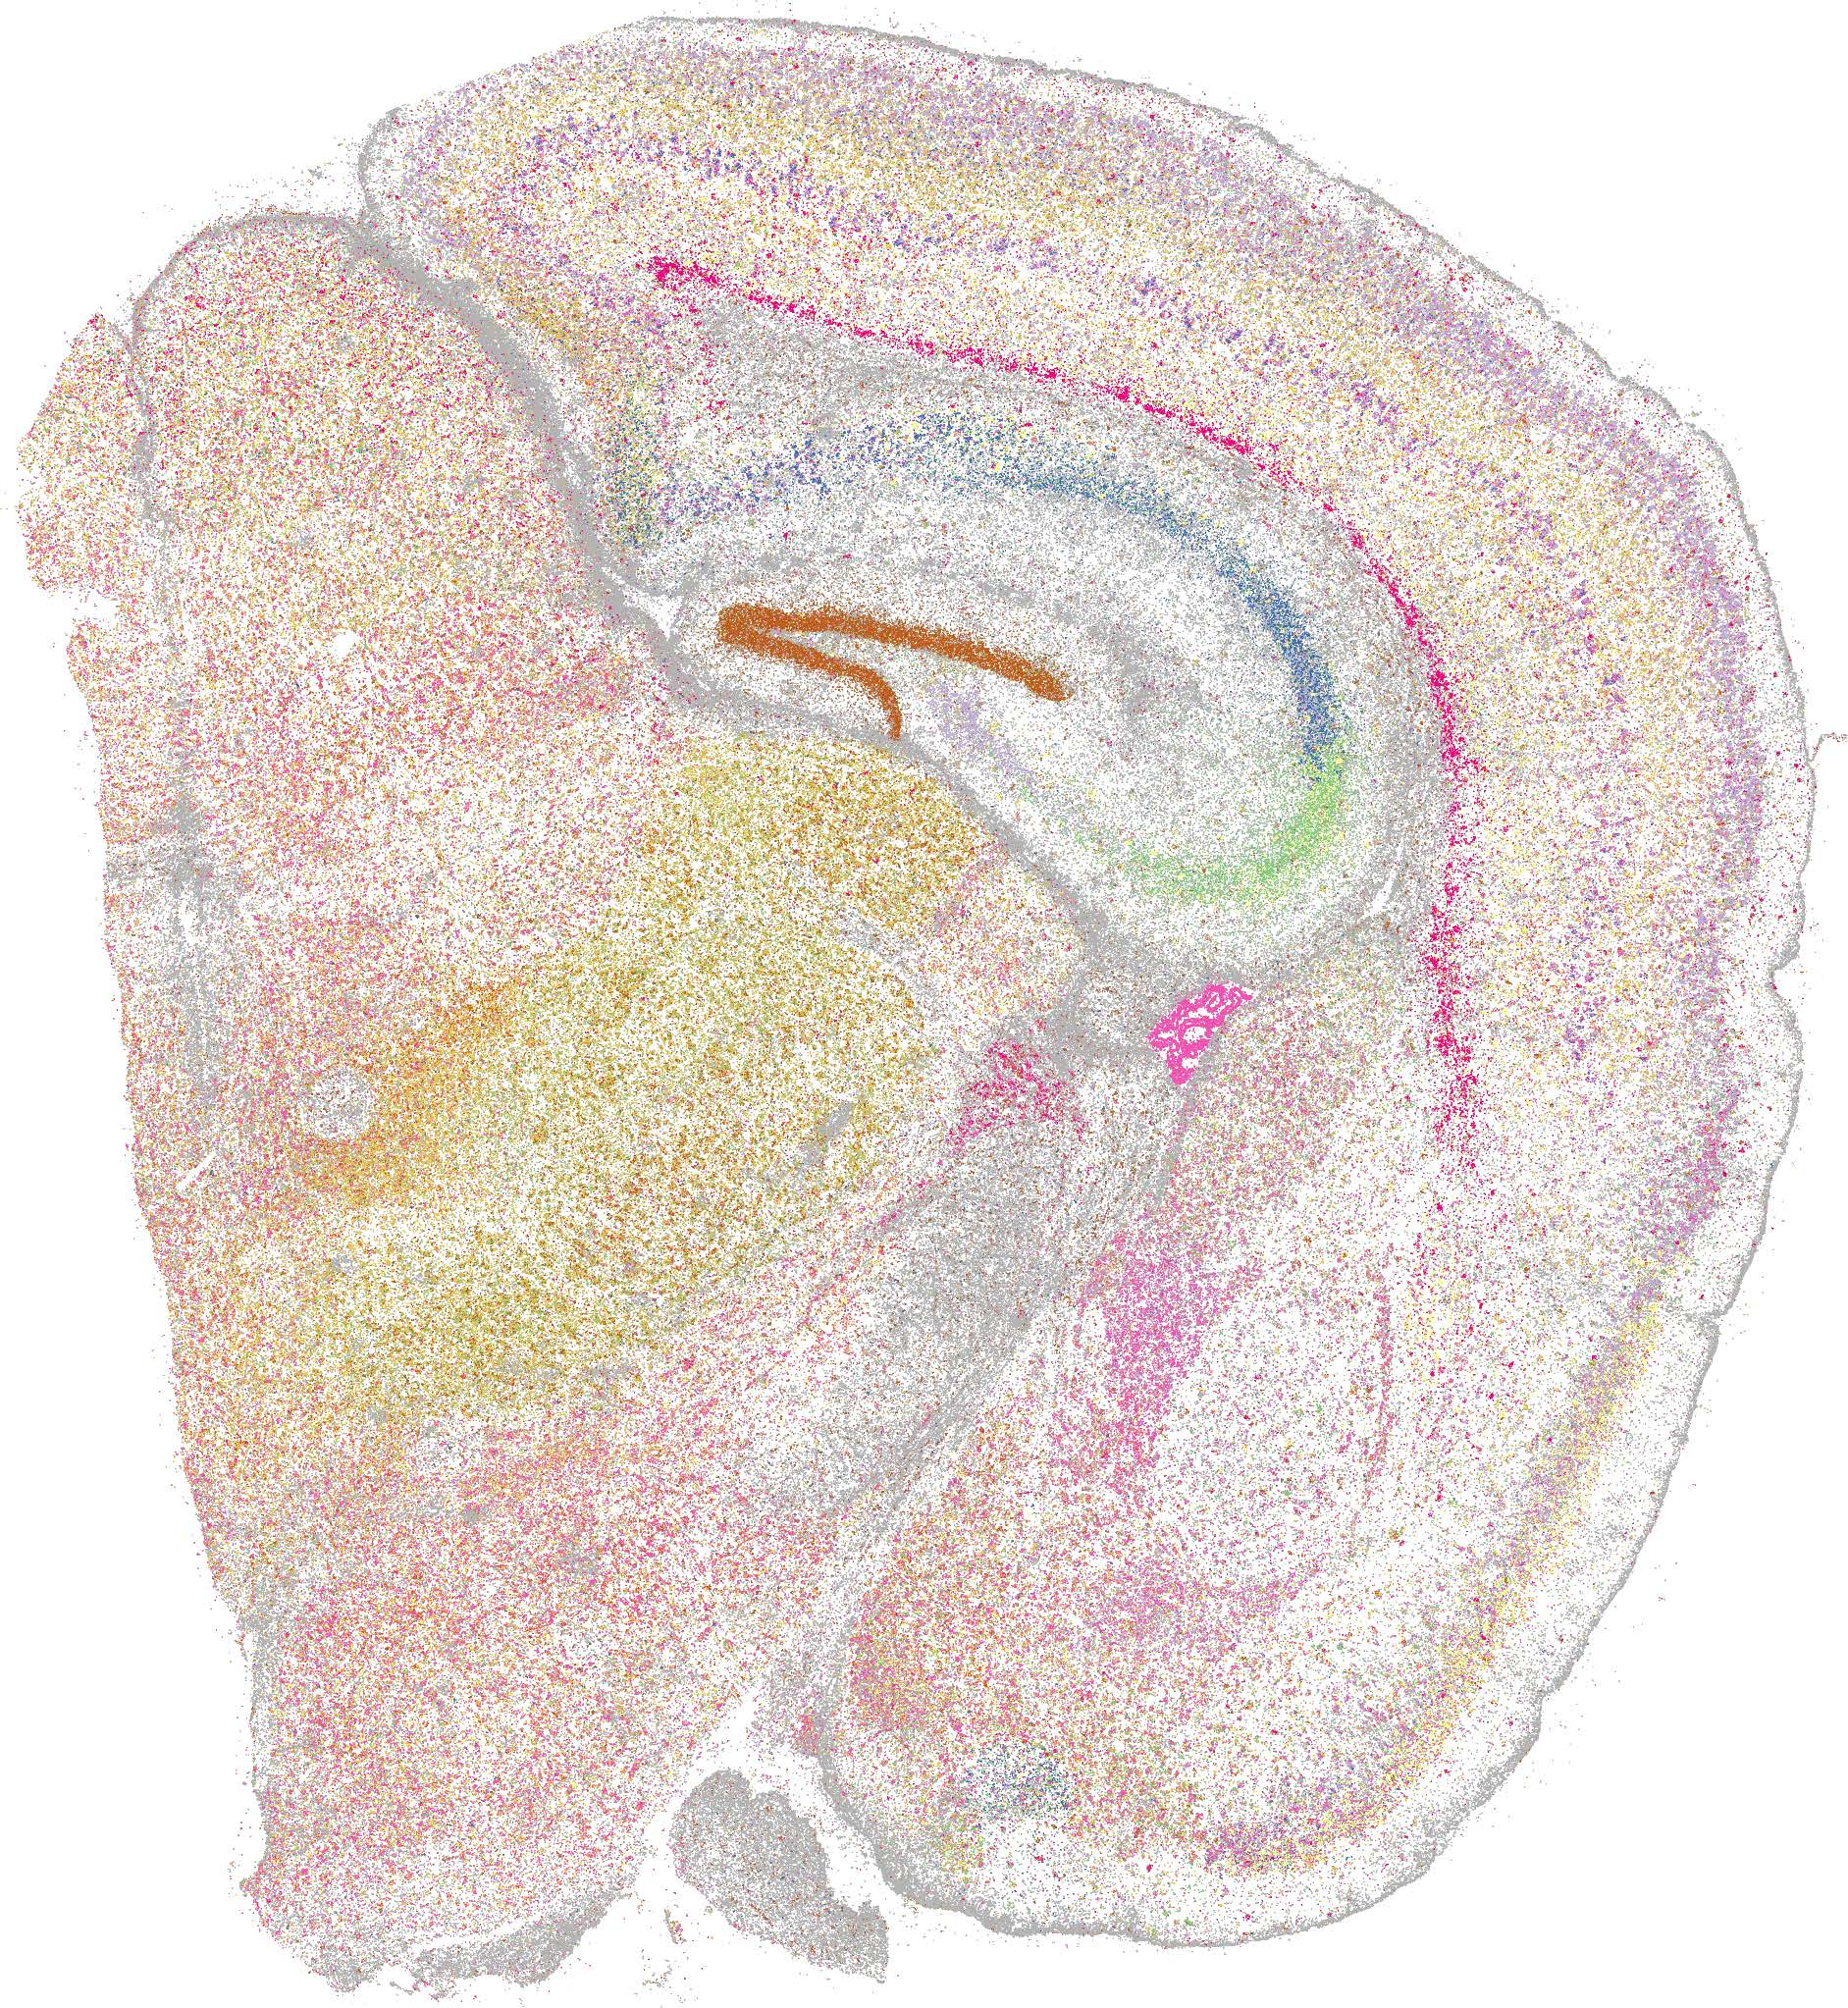

Xenium亚细胞组织原位分析技术结果展示